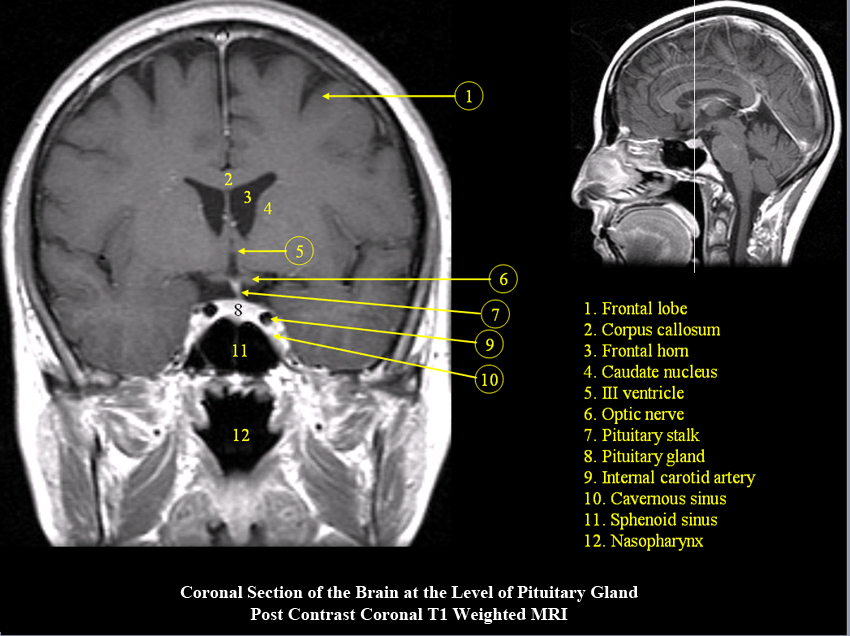

MR Brain and Spine